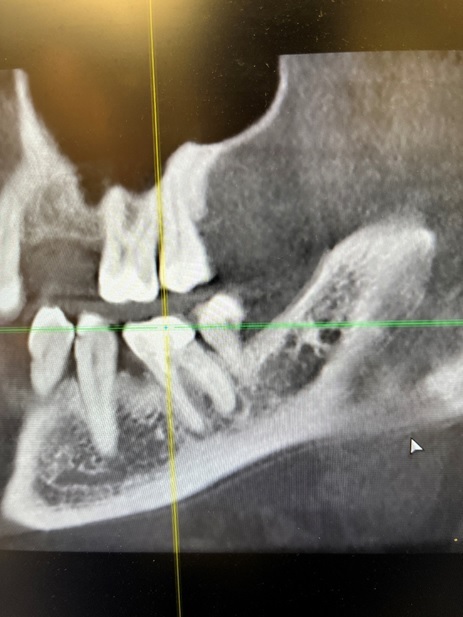

У него было воспаление на корне зуба. Сам зуб скрывался под пломбой — та уже изрядно покололась.

2 ) Плохая герметичность. Смесь мумифицирует нерв, но плохо закупоривает верхушку корня. В процессе затвердевания смесь дает усадку и образовывает пустоты. Поэтому инфекция часто выживает, проникает за верхушку и образовывает кисты.

3 ) Сложно удалить зуб. Высушивание затрагивает не только нерв, но и ткани зуба, и связку, за которую он держится. Зуб становится хрупким, как стекло, и плотно срастается с костью. Удаление превращается в мучение: корень крошится и не хочет выходить целиком. Именно поэтому некоторые коллеги называют резорцин «слеза хирурга».

К сожалению, в городских поликлиниках, а также во всяких дворовых забегаловках сортирного типа с выпиливанием не заморачиваются и выламывают корень вместе с костной стенкой. Остается огромная дыра, которая заживает не одну неделю, а установить потом туда имплант без колдунства с наращиванием кости бывает крайне трудно. Глава 9

5 ) Сложно перелечить. Каналы, не до конца пройденные изначально, закупориваются ещё сильнее. Перелечивание повышает риск перфораций корня или облома инструмента.